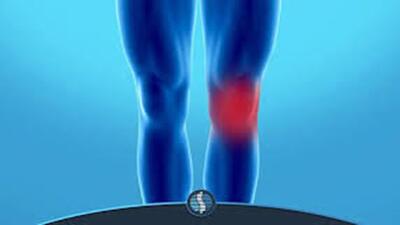

راز تکنیک درمان اورژانسی زانو درد + فیلم

متخصص طب سنتی یک تکنیک درمان اورژانسی زانو درد را آموزش داد.